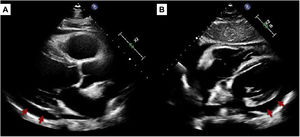

El electrocardiograma a su llegada mostró un ritmo sinusal con elevación del segmento ST generalizada en I, II, aVL, aVF y V2-V6 (fig. 1A). Dados los factores de riesgo cardiovascular, perfil clínico y alteraciones electrocardiográficas se realizó una coronariografía urgente que no mostró lesiones coronarias significativas. Analíticamente destacaba una función renal normal, leve leucocitosis, elevación de reactantes de fase aguda (proteína C reactiva 156,3mg/l, normal: <5mg/l) y discreta elevación de marcadores de daño miocárdico (troponina T de alta sensibilidad 17,7 y 18,1pg/ml, percentil 99: 14pg/ml). Se realizó un ecocardiograma transtorácico en el que se observó un ventrículo izquierdo de dimensiones normales con función sistólica conservada, ausencia de valvulopatías y presencia de pericardio hiperrefringente con derrame pericárdico moderado (fig. 2). Posteriormente al cateterismo presentó rachas autolimitadas de fibrilación auricular. Se decidió mantenerlo ingresado durante 48h para valorar la evolución y la respuesta al tratamiento.

Durante el ingreso presentó mejoría clínica tras el inicio de antiinflamatorios. Se pautó ibuprofeno y colchicina, siguiendo las recomendaciones actuales6. Mediante un panel básico de autoinmunidad y serología se descartaron otras causas de miopericarditis. Se repitió la ecocardiografía a las 48h, sin mostrar cambios respecto a la previa. Dada la evolución favorable, se decidió alta con seguimiento ambulatorio. Tras completar 3 meses de tratamiento, se encontraba asintomático, con normalización de marcadores de daño miocárdico y reactantes de fase aguda, y habiendo corregido los cambios electrocardiográficos (fig. 1B). Permanecía un ligero derrame pericárdico residual en la ecocardiografía de control.